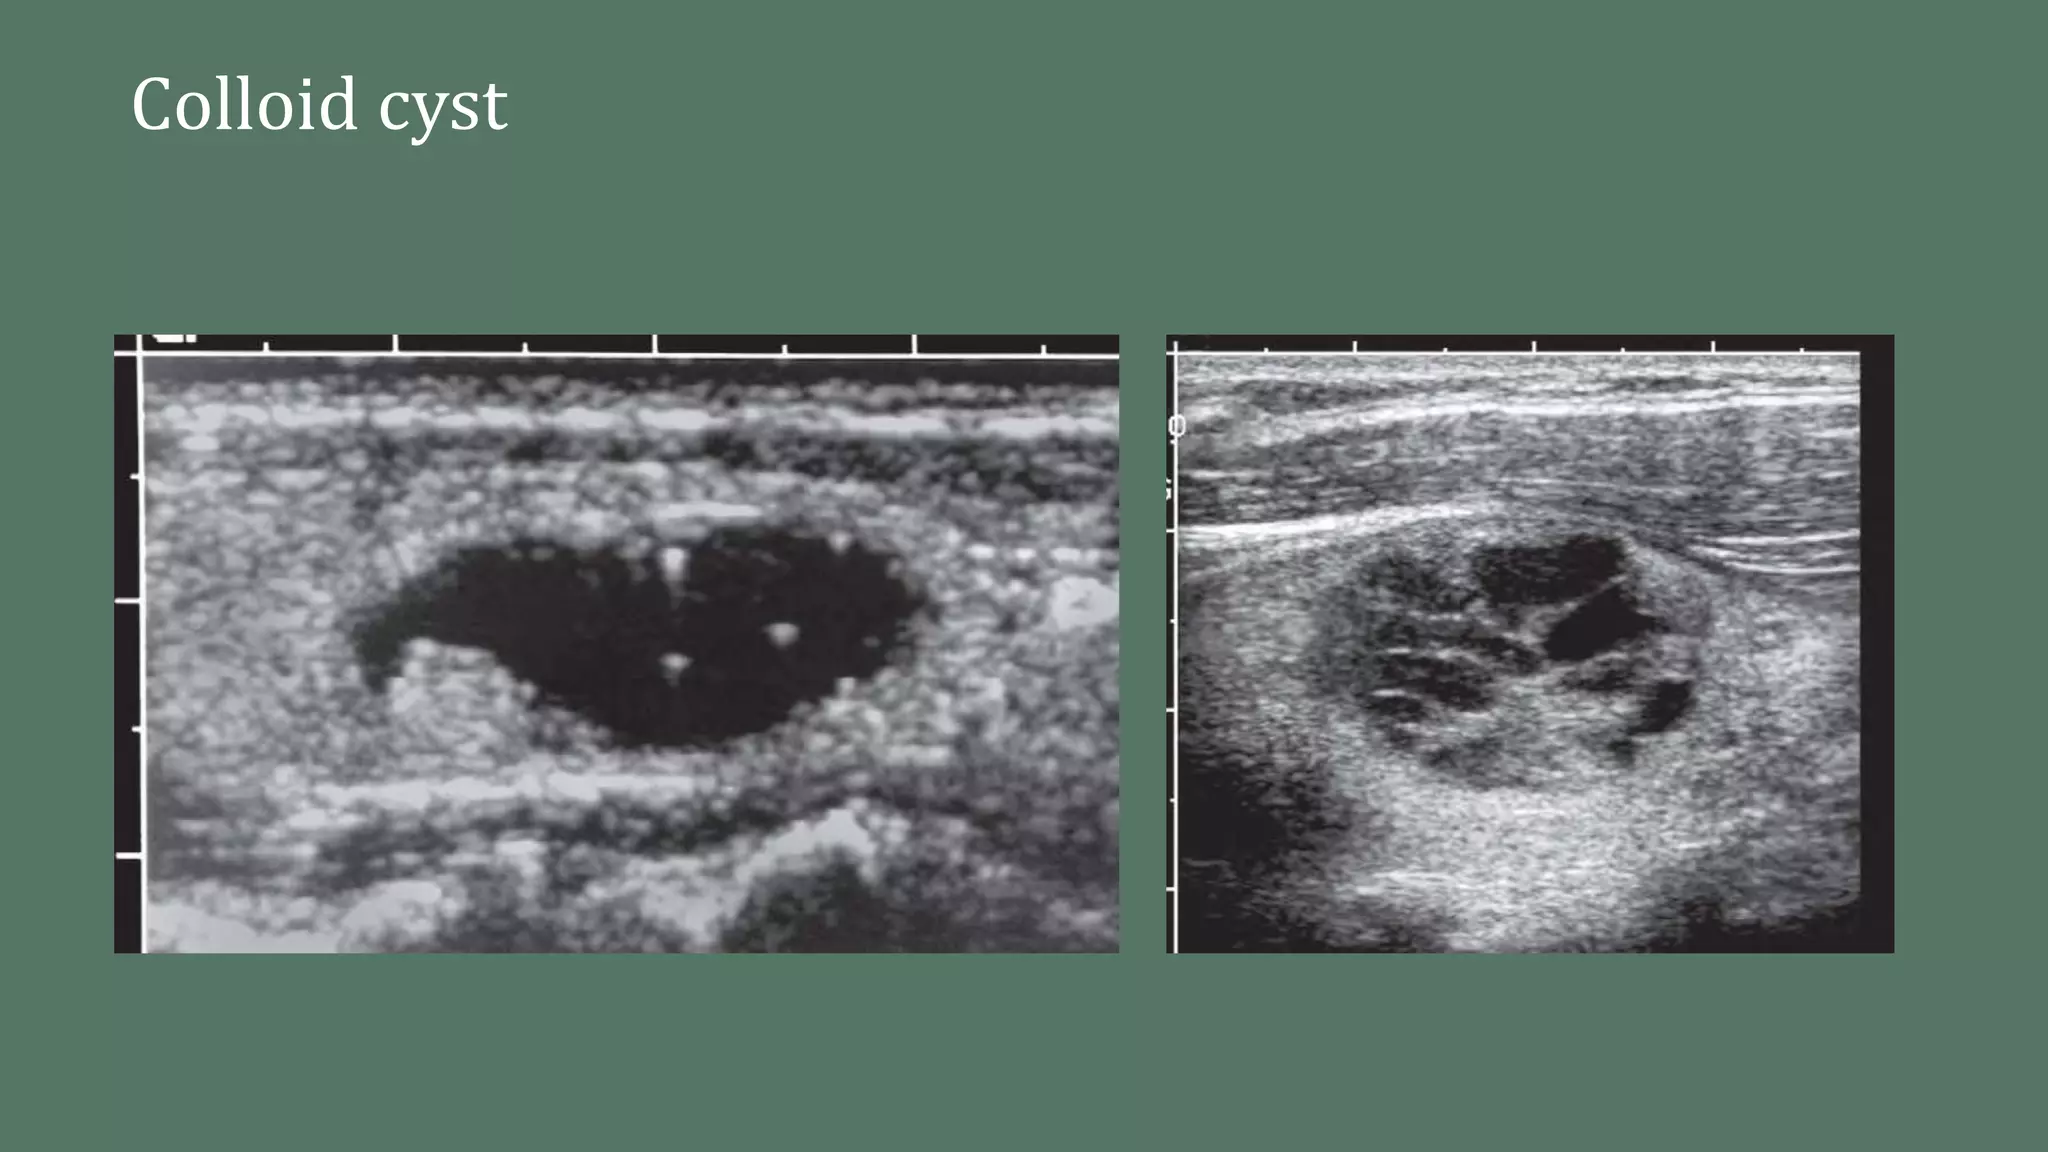

A Thyroid Gland Colloid Cyst is a fluid-filled sac that develops within the thyroid gland. These cysts are typically benign and are often filled with a colloid substance, which is a thick, gelatinous material produced by the thyroid gland. Colloid cysts can vary in size and may not always cause symptoms, but when they do, they can lead to discomfort and other health issues.

• Ultrasound: This imaging test uses sound waves to create detailed images of the thyroid gland, helping to identify the presence and characteristics of the cyst.